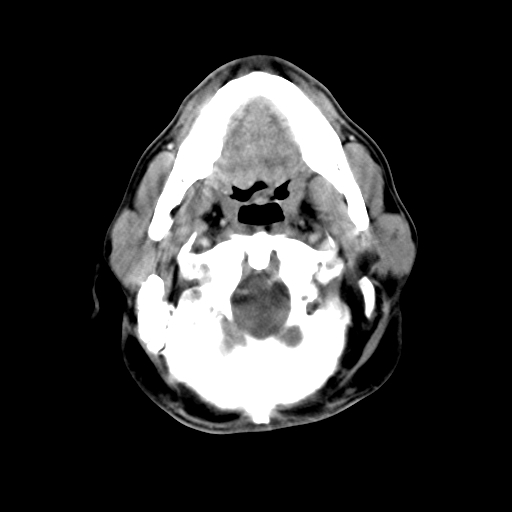

标题: CT24019:男,45岁,发现颈部肿物5个月。 [打印本页]

男,45岁,发现颈部肿物5个月,彩超示:双侧颈部及下颌部软组织增厚。

考虑双侧颈项部良性对称性脂肪增多症。